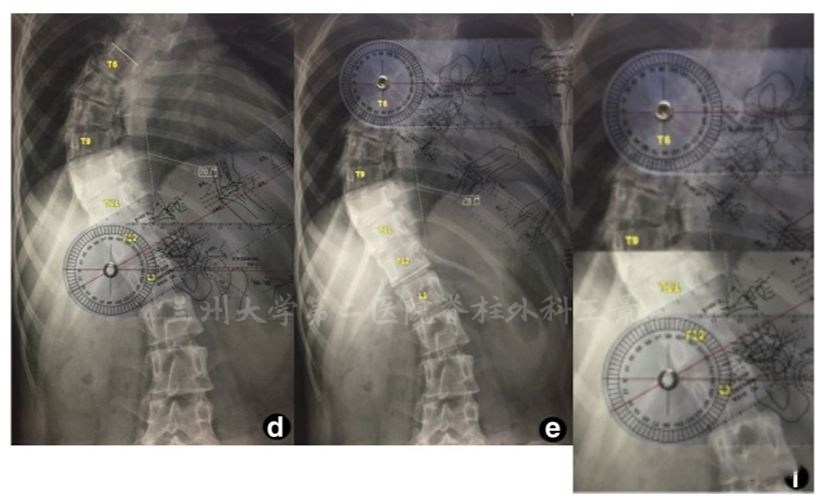

实际操作中的快捷方法

量角器底边放胶片上摆平

角度刻度线与端椎终板吻合后直接读数

水平线都不用画了,几秒钟时间

这种利用端椎倾斜角度的测量原理

可以用在手机上更直接快速的测量Cobb角

如法炮制,拍照测量脊柱侧弯Cobb角

为方便演示,照片标注上、下端椎终板连线

旋转照片使终板连线和网格线重叠

读出上、下端椎的倾角绝对值

相加后就是Cobb角